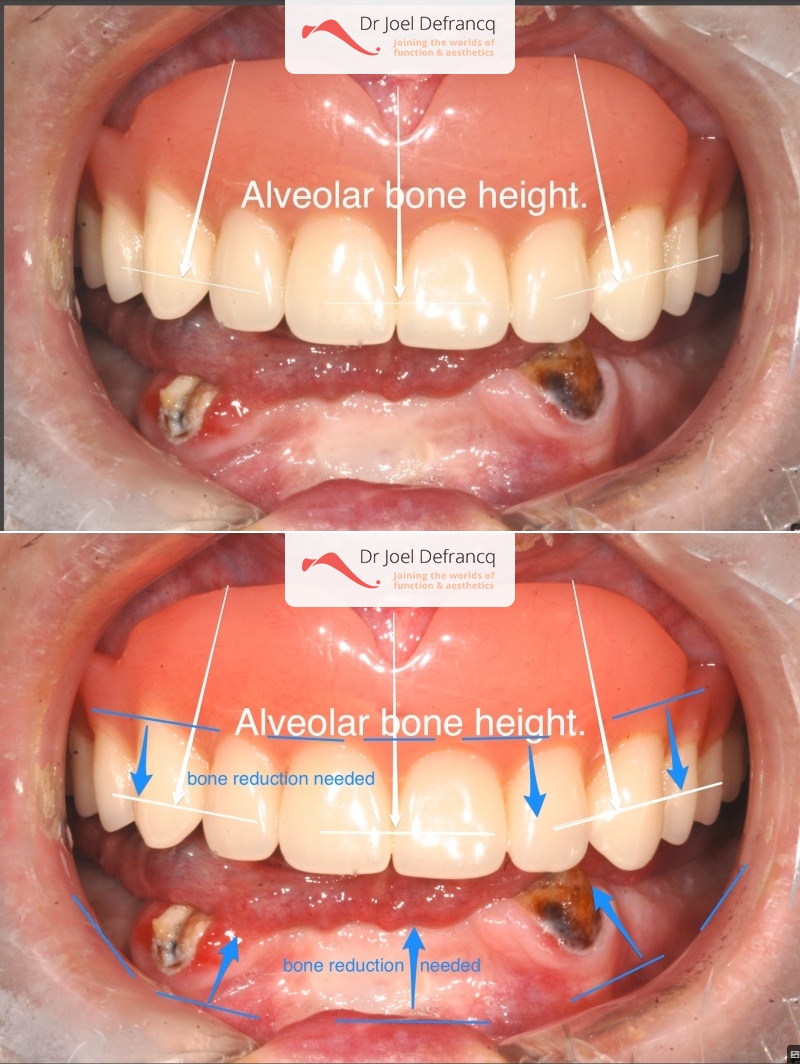

Behandeling tandheelkundige implantaten

- Vaste tanden op implantaten (bovenkaak)

- Vaste tanden op implantaten (onderkaak)

- Implantaten met osteotomie